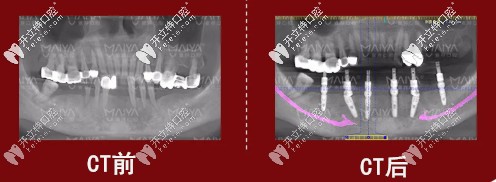

種植前后對(duì)比圖

種植牙前后對(duì)比圖